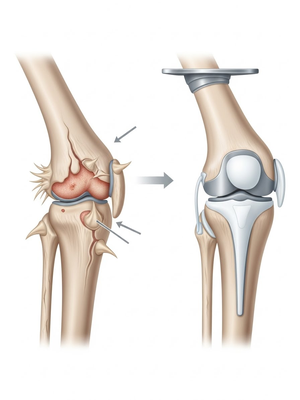

Aşınmış, hasar görmüş ya da eklem yüzeyleri tamamen bozulmuş diz ekleminin, yapay bir eklemle değiştirme işlemidir. Ameliyatta, ağrıya neden olan hasarlı kemik ve kıkırdak dokular çıkarılarak; yerine metal ve özel plastikten yapılmış, uzun ömürlü bir protez yerleştirilir. Bu sayede diz, tekrar ağrısız ve stabil bir şekilde çalışır hale gelir.

Eklem yüzeyleri özel kılavuzlar yardımı ile temizlendikten sonra metal protez eklem yüzeylerine bir kemik çimentosu ile adapte diyoruz. Bu iki metal yüzeyin sürtünmesini azaltmak için polietilenden yapılmış özel bir plastik tabakayı sisteme dahil ediyoruz.